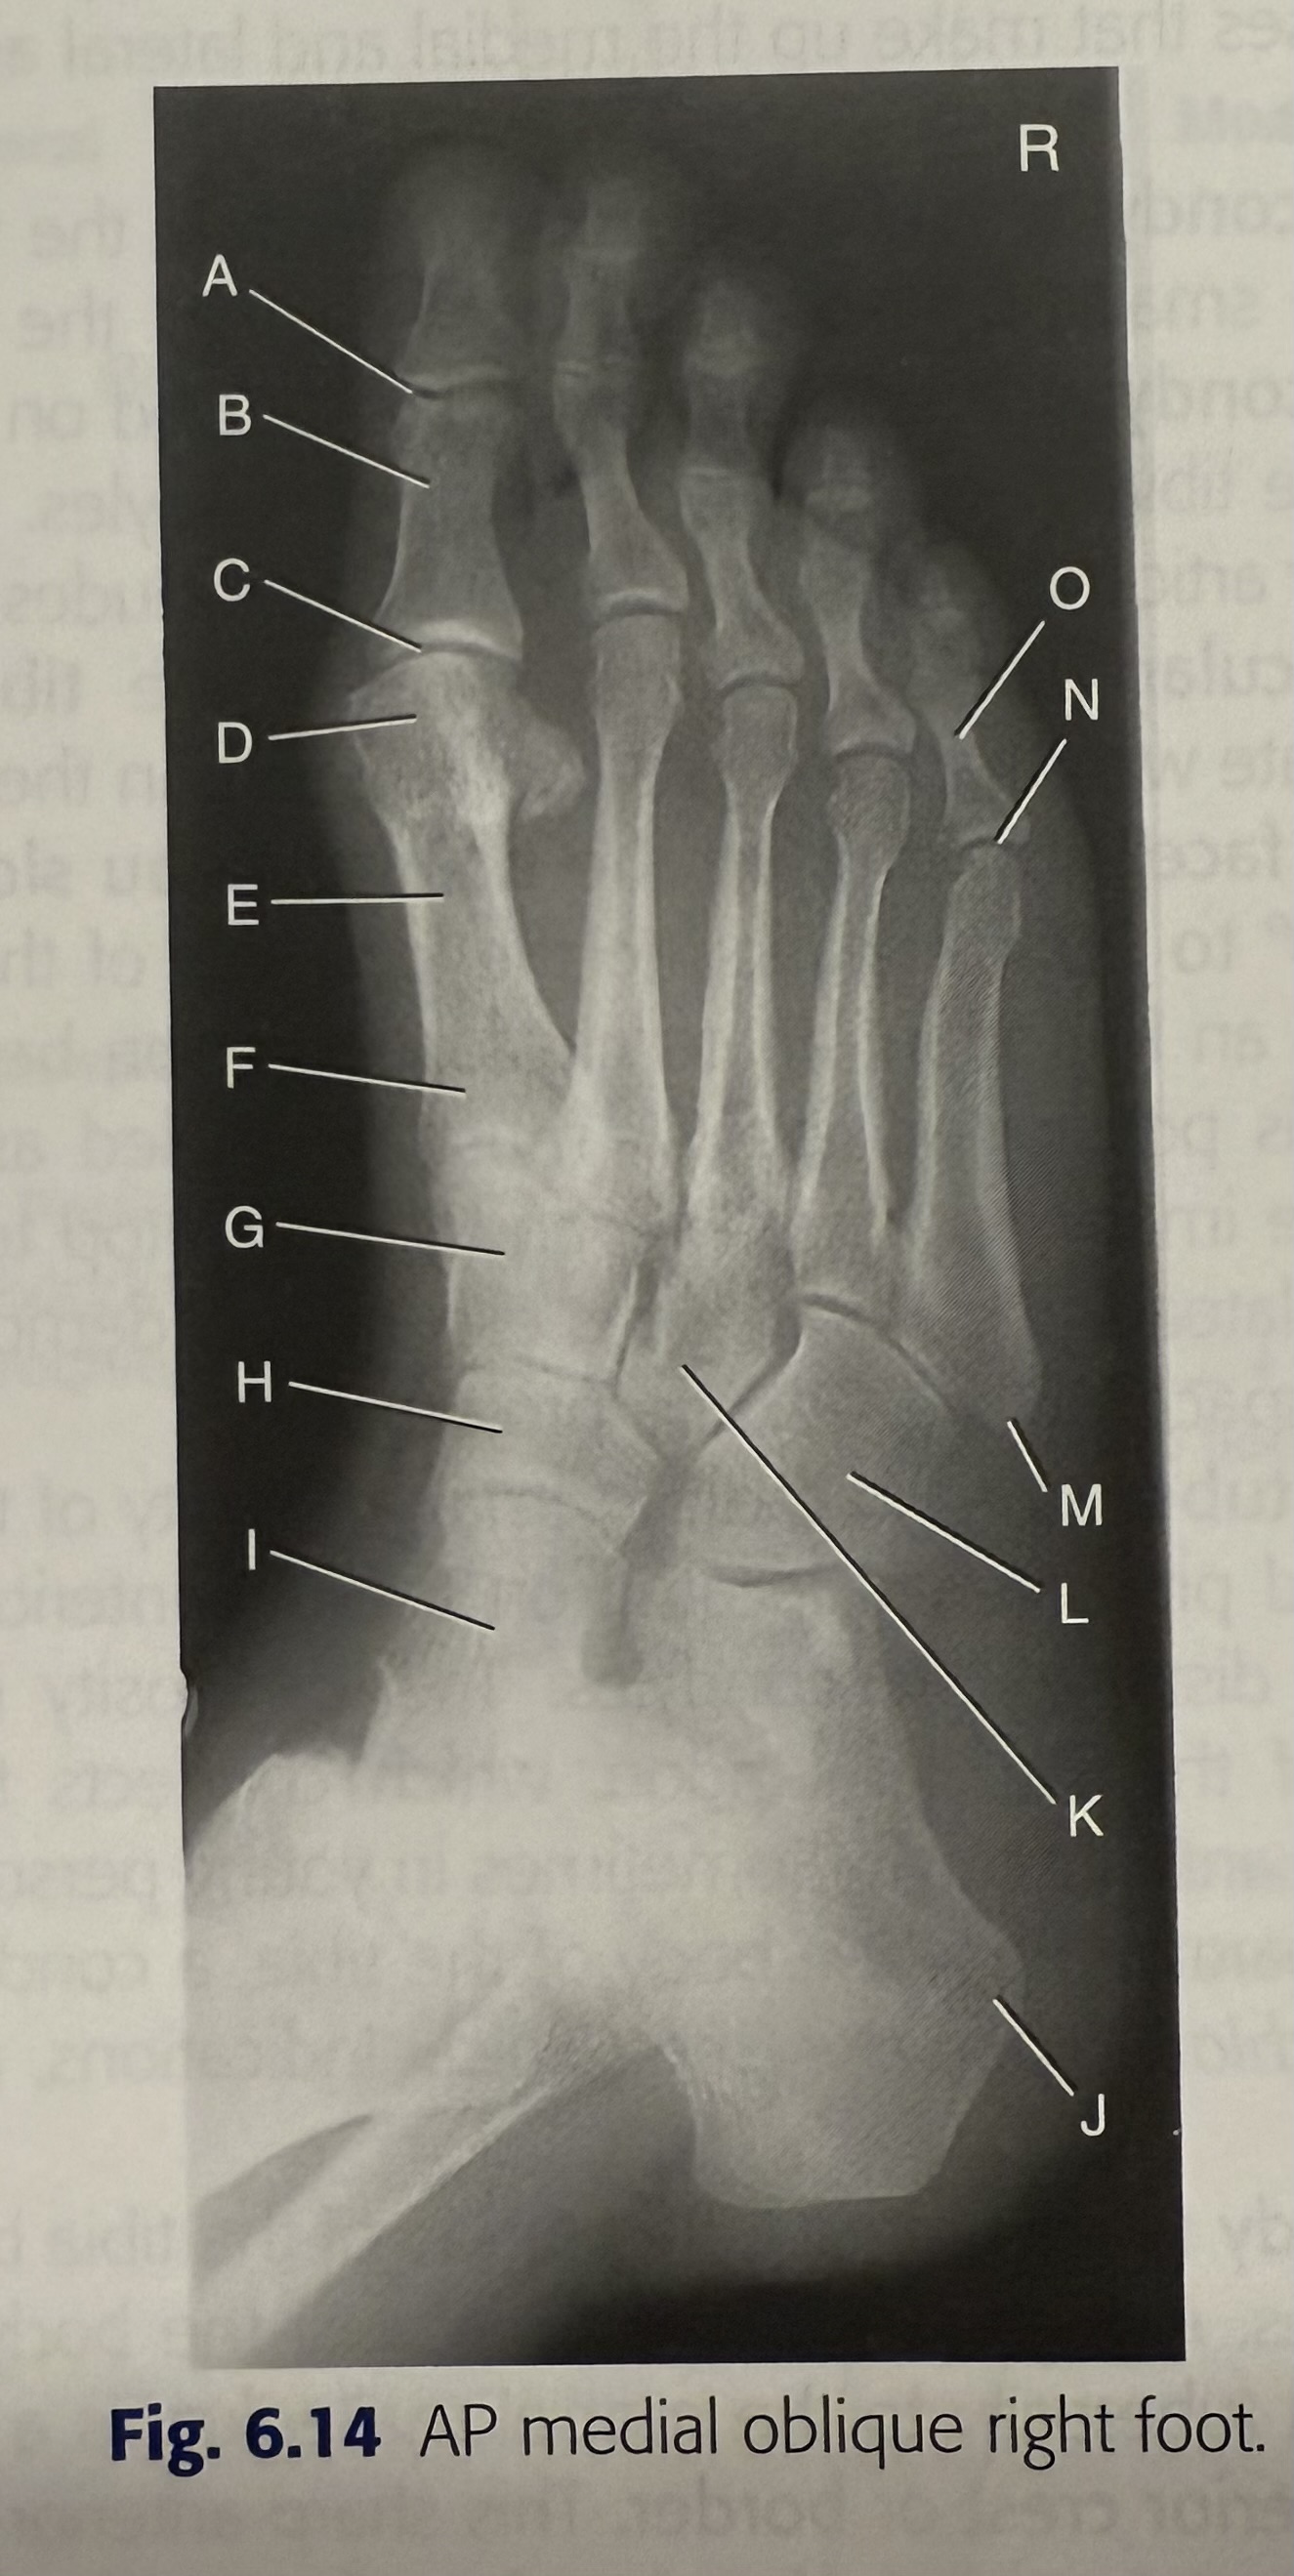

<p>A</p>

A

IP joint

New cards

<p>B</p>

B

MTP joint

71

<p>C</p>

C

3rd TMT joint

72

<p>D</p>

D

DIP joint

73

<p>E</p>

E

PIP joint

74

<p>F</p>

F

TMT joints

75